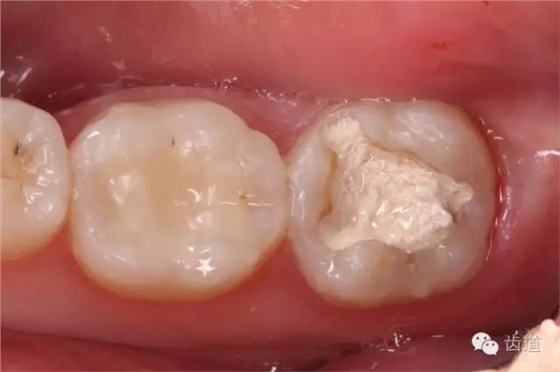

2. 去盡暫封及原充填物,發(fā)現(xiàn)近中頰側(cè)壁較薄,有無基釉殘余

3. 制備嵌體洞型,去盡無基釉

4. 精細(xì)修整洞型